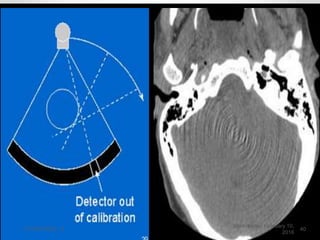

RING ARTEFACT

• Result of miscalibration of a detector

.

• Records incorrect data in every

position .

• The misinformation is reconstructed

as a ring in the image .

• The radius of the ring determined by

the position of the faulty detector .

RING ARTEFACT • Resultof miscalibration of a detector . • Records incorrect data in every position . • The misinformation is reconstructed as a ring in the image . • The radius of the ring determined by the position of the faulty detector . Wednesday, February 10, 2016 CT PHYSICS - II 39